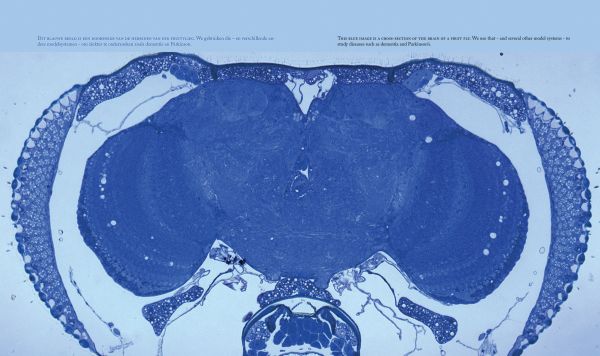

The brain is a miracle, a universe that appeals to everyone’s imagination, and one that neuroscientists never tire of exploring. And the more detailed our knowledge of it gets, the more technology advances that enables us to visualize what goes on inside the brain, the more fascinating and intriguing it becomes. This book, created at the Belgian Leuven Brain Institute (LBI), contains breathtaking and inspiring images and vivid text to reveal the current state of international brain research. It features contributions from world-class researchers, full of facts and unique insights.